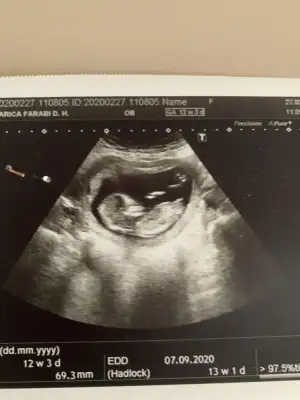

Ikra meyra Ikra meyra Bizede bakar mısınız? Daha öncede göndermiştim başka istemiştiniz. İki kızım var inşallah erkektir hayırlısı😊

• F42B9FC0-2405-489D-BEEA-249F6257E87D.webp

F42B9FC0-2405-489D-BEEA-249F6257E87D.webp

26,6 KB · Görüntüleme: 64

• 25CFF45F-B991-40B0-AB78-C7E3CAB725B9.webp

25CFF45F-B991-40B0-AB78-C7E3CAB725B9.webp

32,2 KB · Görüntüleme: 65

Merhaba detaylıda kız dedi doktor, anketi doğru tahmin olarak işaretledim. Teşekkürler😁

Saglıkla gelsin prenses 😊😊 ilk kız dedim teyit etmek için başka usg istemiştim. Teşekkurler dönüşler için 😊